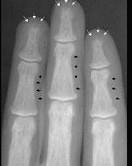

问题 下列哪项X线表现对甲状旁腺功能亢进症有诊断价值()

选项 A.弥漫性脱钙 B.纤维囊性骨炎 C.骨囊肿样变化 D.骨膜下皮质吸收、颅骨斑点状脱钙 E.多发性骨折或骨骼畸形

答案 D